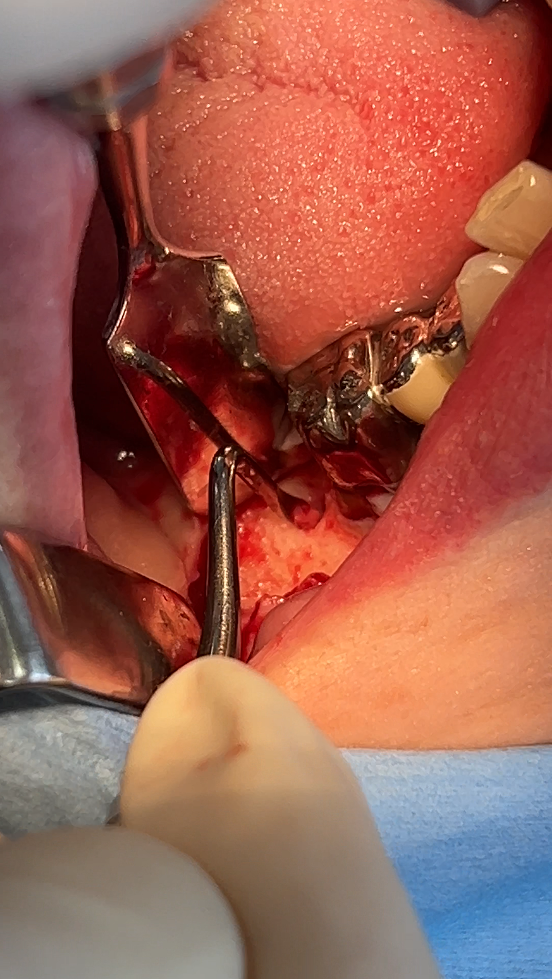

⻭⾁剥離掻爬

デコルチケーション

掻爬・デコルチ完了

⾻補塡材に上清液を混和

抜⻭窩に⾻補填材